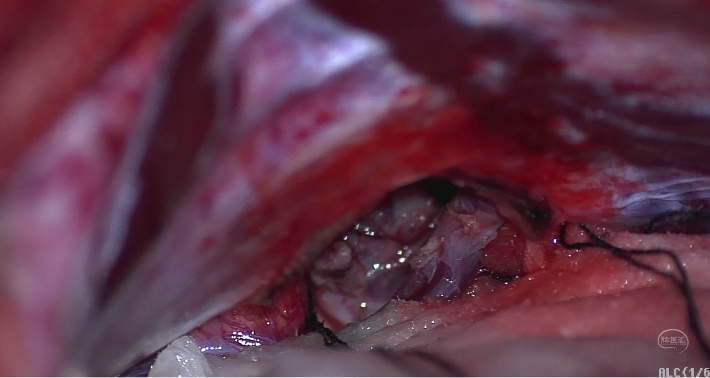

解剖蛛网膜后暴露松果体区域肿瘤病变。

切除松果体区病变后显示三脑室后部区域及重要静脉保护情况。